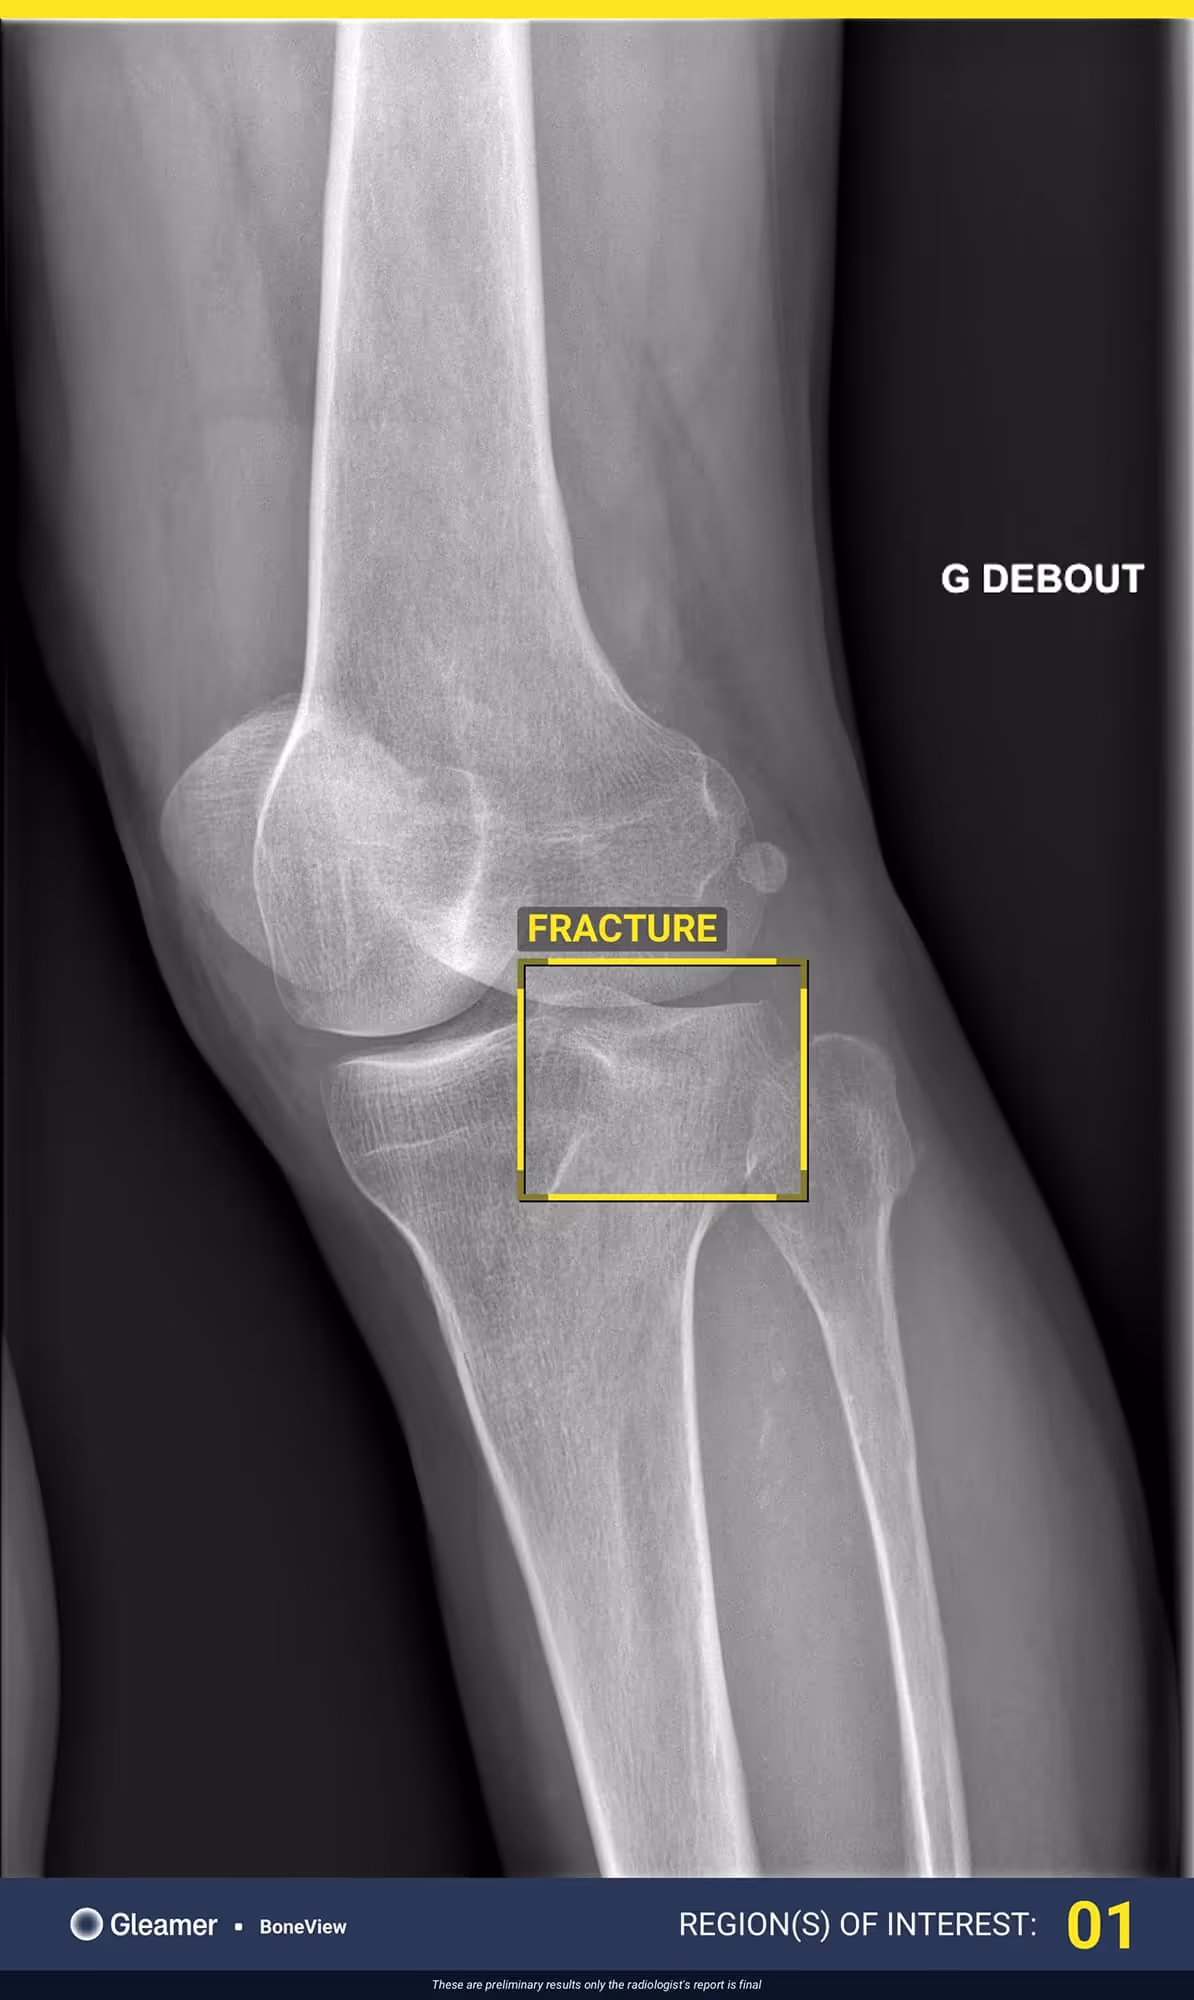

A 63-year-old male with lingering pain after a trail run.

BoneView detected a fracture of the lateral tibial plateau and associated effusion. The fracture has a high risk of displacement.